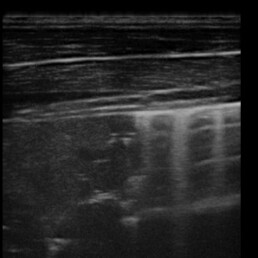

Weiterführende Untersuchungen: Sonographie

- wir stellten "Kometschweifartefakte" fest, die uns einen Hinweis auf zelluläre Infiltration liefern

- Kontrolluntersuchung der entsprechenden Stellen mit Ultraschall